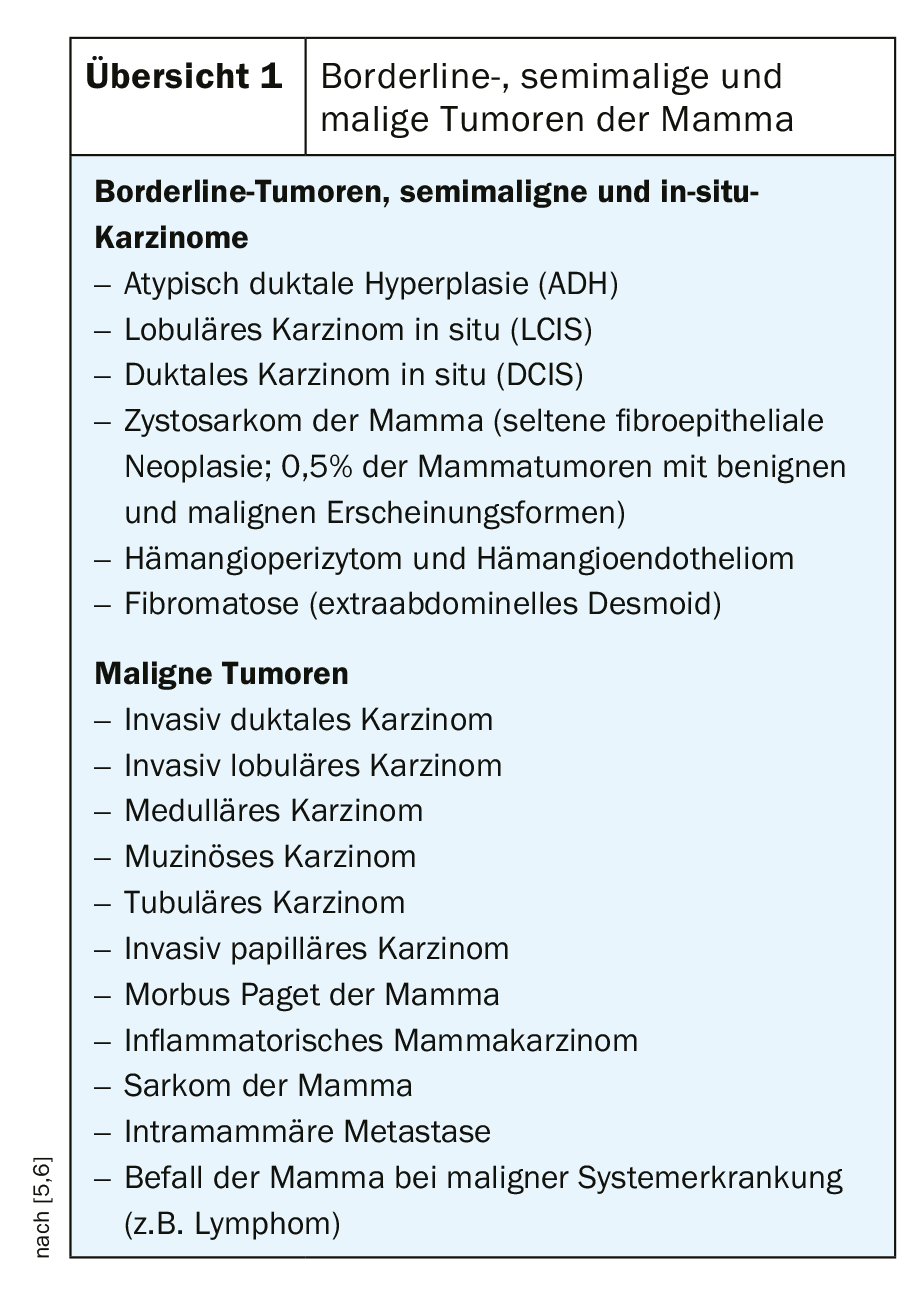

Os diferentes tipos histológicos (panorâmica) de tumores limítrofes, semi-malignos e malignos nem sempre podem ser diferenciados imagem-morfológica-morfologicamente. É crucial que eles sejam reconhecidos e que o curso seja definido para procedimentos de diagnóstico ou terapêuticos posteriores, se necessário.

- Numerosas alterações malignas podem ocorrer na mama.